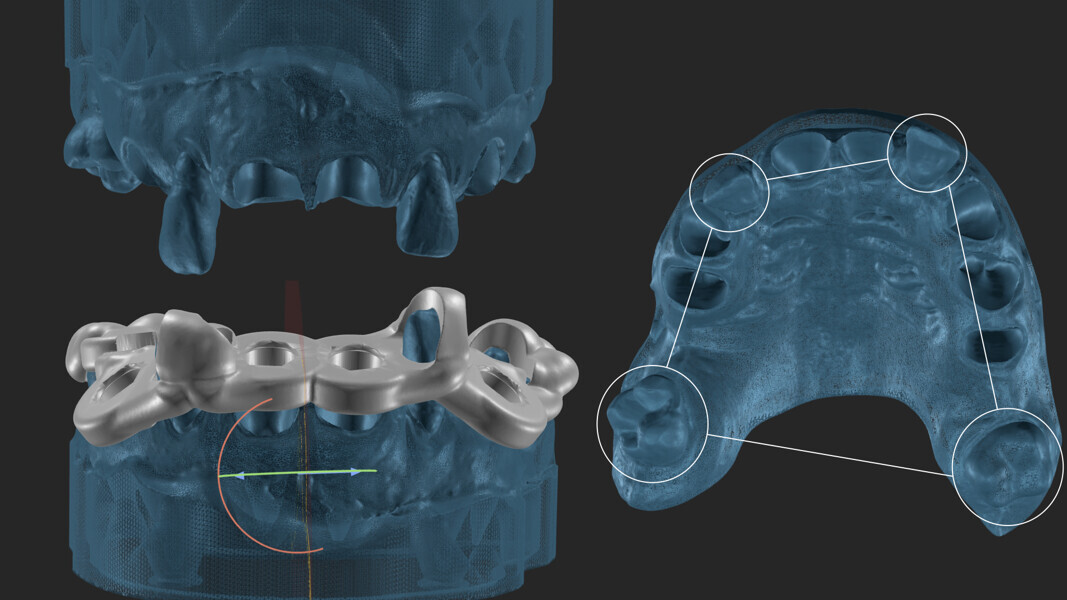

For effective 3D planning, having a combined extraction model is essential. This provides the dental technician with clear reference points for creating custom support that follows the emergence profile of each individual tooth (Figs. 6 & 7).

In this specific case, we strategically positioned the design palatally and more coronally. This compensated for the existing occlusal disharmonies while also shaping the soft tissue for prosthetically guided healing of the extraction sites. By integrating these adjustments, we could harmonise the patient’s bite and smile, achieving both function and aesthetics (Figs. 8–10).

Fig. 6: Combination of the CBCT and the intra-oral scans for segmentation.

Fig. 7: Combined extraction model.